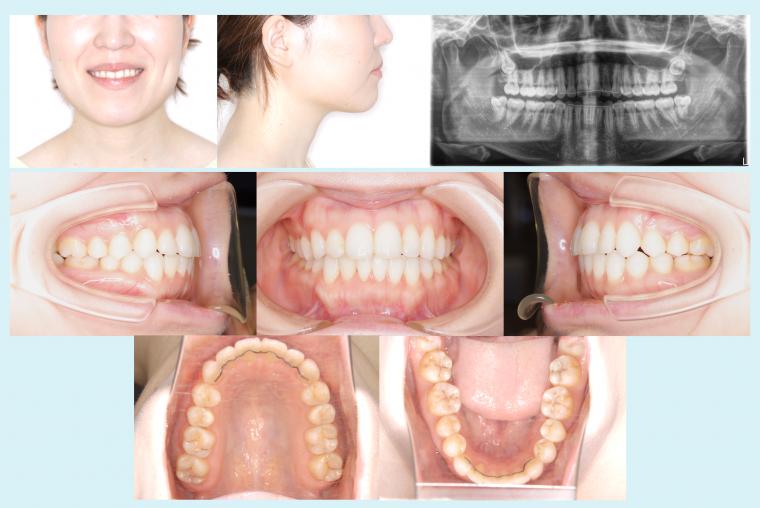

#50 非抜歯で叢生を改善した症例